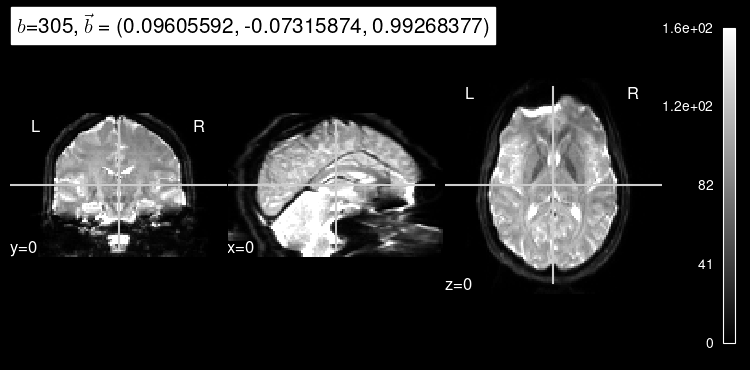

Finally, we can generate our registration reference with the predict()

method:

predict_b = np.squeeze(data_test[2])

predicted = model.predict(predict_b)

plot_dwi(predicted, dmri_dataset.affine, gradient=predict_b);

As expected, the b=0 doesn’t look very much like the particular left-out direction, but it is a start!